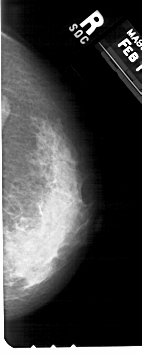

A_1238_1.RIGHT_MLO

RIGHT_CC LINES 5296 PIXELS_PER_LINE 2116 BITS_PER_PIXEL 12 RESOLUTION 43.5 NON_OVERLAY

RIGHT_MLO LINES 5491 PIXELS_PER_LINE 2356 BITS_PER_PIXEL 12 RESOLUTION 43.5 NON_OVERLAY